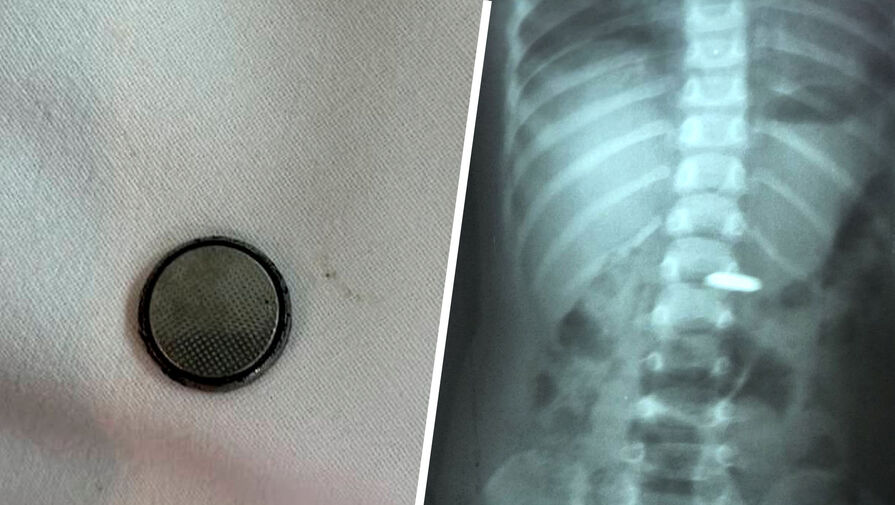

В Саратовской области спасли годовалого ребенка, который проглотил батарейку. Об этом сообщает Балаковская городская клиническая больница.

Все началось с того, что малолетний проглотил батарейку«таблетку» — при каких обстоятельствах это случилось, не уточняется. Ребенка доставили в больницу, где врачи провели ему эндоскопическую операцию и извлекли опасный инородный предмет.

Как пояснила детский врач-хирург, батарейки представляют особую опасность из-за способности вызывать не просто ожоги слизистой, но и глубокие поражения тканей с последующей интоксикацией. Разгерметизация элемента питания с утечкой электролита может произойти уже через 2,5 часа после проглатывания, и это может привести к трагическим последствиям.